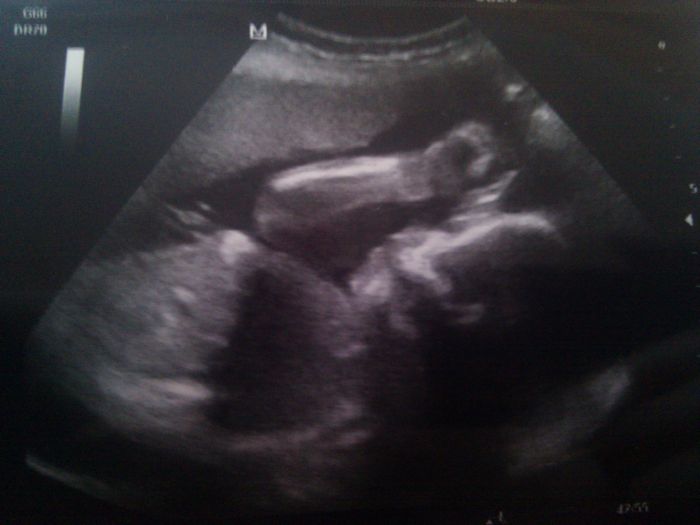

Jinak holky v úterý jsem byla na kontrole, Míšánek má už 600g, přiložím vám sem i fotku. Je to malej rošťáček

[218169] Už jsou velcí ti naši drobečci

Hezká fotečka, za měsíc na tom obrázku už bude jen hlava

[218175] No to teda jo, rostou jako z vody, zlatíčka malinký

pamatuju si, když ještě byl na UTZ jen "prstýnek"

a teď? teď jsou to rošťáci divocí ... Achjo holky, já už se tak těším, až toho Míšánka budeme mít doma, teda ne že bychom ho teď neměli, ale ještě je v bříšánku.

[218169] Ty jo, Verus, takze dnes uz ma malickej uz tak pres 600 g? Tak to je krasa! Ja Bunika dle posledniho odhadu z UZ pred 14 dny odhaduju dnes tak na pul kila teprve. Koneckoncu syn byl (a je) taky hubenour :) S tim zvracenim jsme na tom podobne. Ja nezvracim asi tak od toho velkeho UZ, tzn. cca dva tydny. Snad jsem to ted nezakrikla. Srandovni je, jak je cloveku fakt dobre, tak uz si nastesti na to zvraceni moc nevzpomene. Ale i tak to za to stalo. Tehotenstvi je proste tak moc krasny stav, aspon pro me... ted si uzivam kazdy den a je mi pomalu lito, ze uz jsme za pulkou.